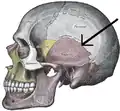

Side view of the skull. Squamosal suture indicated by the black arrows.